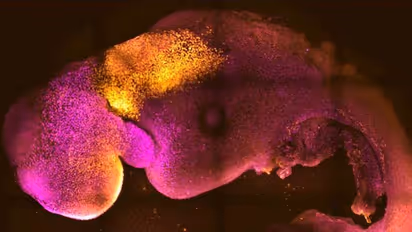

ബീജവും ഗര്ഭപാത്രവുമില്ലാതെ പുതിയൊരു ജീവന്റെ തുടിപ്പിനെക്കുറിച്ച് നമുക്ക് ഇതുവരെയും ചിന്തിക്കാനെ ആകുമായിരുന്നില്ല. എന്നാല് ഇപ്പോഴിതാ അതും സാധ്യമണന്ന് തെളിയിച്ചിരിക്കുകയാണ് ശാസ്ത്ര ലോകം. ബീജവും ഗര്ഭപാത്രവുമില്ലാതെ എലിയുടെ സിന്തറ്റിക് ഭ്രൂണം ശാസ്ത്രജ്ഞര് വിജയകരമായി വളര്ത്തിയിരിക്കുകയാണ്. ജീവിതത്തിന്റെ ആദ്യ ഘട്ടം പുനഃസൃഷ്ടിക്കാന് അവര് എലികളില് നിന്നുള്ള സ്റ്റെം സെല്ലുകള് ഉപയോഗിച്ച് മസ്തിഷ്കം, മിടിക്കുന്ന ഹൃദയം, മറ്റ് അവയവങ്ങള് എന്നിവയുള്ള ഭ്രൂണമാണ് കാംബ്രിഡ്ജ് സര്വകലാശാലയിലെ ശാസ്ത്രജ്ഞര് വിജയകരമായി വികസിപ്പിച്ചിരിക്കുന്നത്.

ജീവന്റെ സ്വാഭാവിക പ്രക്രിയയായ അണ്ഡ- ബീജ സങ്കലനം ഇല്ലാതെയാണ് ശാസ്ത്രജ്ഞര് ലാബില് എലിയുടെ ഭ്രൂണം വികസിപ്പിച്ചെടുത്തതത്. ശരീരത്തിലെ മാസ്റ്റര് സെല്ലുകള് ഈ പ്രക്രിയയിലെ നിര്ണായക ഘടകമാണ്. ഇവ ശരീരത്തിലെ മറ്റ് അവയവങ്ങളുടെ വളര്ച്ചയ്ക്ക് കാരണമാകുന്നു. ബീജസങ്കലനത്തിനു ശേഷം എട്ടര ദിവസങ്ങള്ക്ക് ശേഷമാണ് ഭ്രൂണം വികസിപ്പിച്ചെടുത്തത്. അതില് സ്വാഭാവിക ഘടനയുടെ അതേ സ്വഭാവം അടങ്ങിയിരിക്കുന്നു.

ഈ നേട്ടം സസ്തനികളുടെ വികാസത്തെ പുനര്നിര്മ്മിക്കുന്നതിനുള്ള ഭ്രൂണത്തിന്റെയും രണ്ട് തരം എക്സ്ട്രാ-എംബ്രിയോണിക് സ്റ്റെം സെല്ലുകളുടെയും സ്വയം-ഏകോപന കഴിവ് തെളിയിക്കുന്നു എന്നാണ് നേച്ചര് ജേണലില് പ്രസിദ്ധീകരിച്ച പഠനം പറയുന്നത്.

'ഞങ്ങളുടെ എലി ഭ്രൂണ മാതൃക തലച്ചോറിനെ മാത്രമല്ല, മിടിക്കുന്ന ഹൃദയത്തെയും, ശരീരത്തെ നിര്മ്മിക്കുന്ന എല്ലാ ഘടകങ്ങളെയും വികസിപ്പിക്കുന്നു. ഞങ്ങള് ഇത് വരെ എത്തി എന്നത് അവിശ്വസനീയമാണ്. ഇത് ഞങ്ങളുടെ വര്ഷങ്ങളായുള്ള സ്വപ്നമാണ്, ഒരു പതിറ്റാണ്ടായി ഞങ്ങളുടെ ജോലിയുടെ പ്രധാന ശ്രദ്ധാകേന്ദ്രമാണ്, ഒടുവില് ഞങ്ങള് അത് ചെയ്തു.' പുതിയ നേട്ടത്തില് സന്തോഷമറിയിച്ചുകൊണ്ട് ഗവേഷണത്തിന് നേതൃത്വം കൊടുത്ത കാംബ്രിഡ്ജ് സര്വകലാശാലയിലെ ഫിസിയോളജി വിഭാഗത്തിലെ മാമല്ലിയന് ഡവലപ്മെന്റ് ആന്റ് സ്റ്റെം സെല് ബയോളജി പ്രൊഫസര് സെര്നിക ഗേറ്റ്സ് പറയുന്നു.